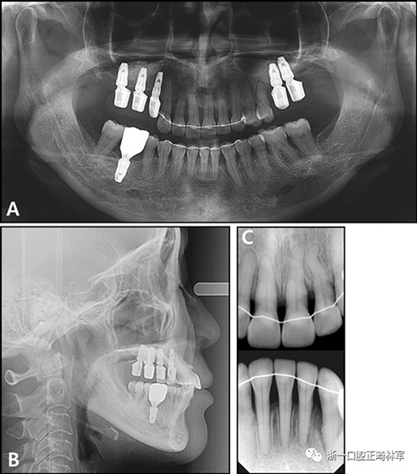

治療后全景X線片顯示與初始值相比,沒有顯著的骨喪失。上頜尖牙被推入并向遠中移動,導(dǎo)致在根尖周觀察到尖牙骨水平的改善。在拔除的下頜側(cè)切牙周圍出現(xiàn)嚴重的牙槽骨缺損,并且尖牙近中側(cè)的牙周病引起了骨內(nèi)缺損。在關(guān)閉間隙期間,下頜中切牙和尖牙被移向了骨質(zhì)缺損區(qū)域,并且側(cè)切牙周圍的缺損已被恢復(fù)(圖12)。此外,尖牙的牙齦退縮臨床上也得到了改善(圖13)。

圖12.治療后的X線片:A,全景X光片;B,頭影側(cè)位片;C,根尖片

治療后頭影測量分析顯示上頜切牙的傾斜和唇部相對于E線的位置都得到改善(表II)。治療前后頭影測量圖的疊加顯示上頜和下頜切牙的向后移動伴隨著上頜切牙的推入。垂直維度在跨學(xué)科正畸綜合治療后被保持。三維模型的疊加顯示了上頜牙列的遠中移動,下頜前牙的回縮和上頜右側(cè)尖牙的推入(圖14)。

根據(jù)治療前后的根尖X光片,可以發(fā)現(xiàn)存在3.5mm顯著改善的放射線骨水平(圖15),并且臨床上牙周袋深度減少(表IV)。此外,力的推入性成分在向遠中移動期間誘導(dǎo)了上頜切牙的推入,并且在根尖X線照片上看到牙槽骨水平的改善。同時,如果種植體首先定位在磨牙區(qū)域,則可以通過使用種植體的臨時修復(fù)作為支抗來控制該力學(xué)過程。這種方法的優(yōu)點在于它解決了患者的主訴,即通過逆轉(zhuǎn)上頜前牙的張開和用最小程度的外科手術(shù)取代缺失的后牙進行咬合來重建咬合和美學(xué)。但是當施加推入力時,在力作用線上施加一個垂直方向的力是不利的。完成整個治療需要花費很多時間,并且在正畸治療期間臨時修復(fù)體可能被破壞。